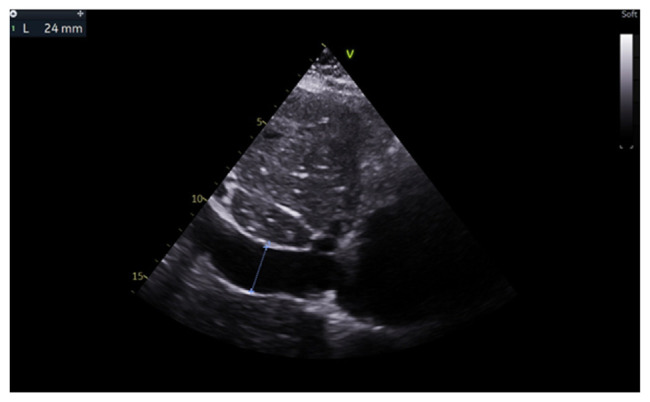

Abstract Image